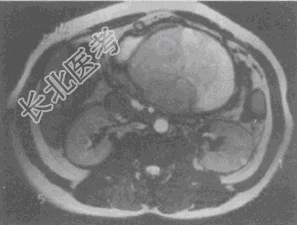

- 单项选择题男,36岁, 腹胀、消化不良、消瘦、中上腹痛,影像检查如下图, 最可能的诊断是

A、胃间质肉瘤并肝转移

B、胃间质瘤并原发性肝癌

C、内胚窦瘤肝转移

D、胃淋巴瘤伴原发性肝癌

E、胃间质瘤并肝血管瘤